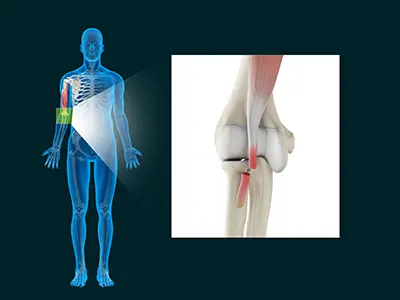

Distal Biceps Repair

The biceps is a large muscle located in the front of your upper arm and runs from the shoulder to the elbow joint.